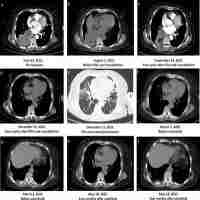

| Abstract | Pulmonary sarcomatoid carcinoma (PSC) is a rare subtype of non-small cell lung cancer with high malignancy and poor prognosis. Chemotherapy or radiotherapy do not usually provide satisfactory results in patients with PSC, especially in those with advanced-stage cancer. Targeted therapy and immunotherapy are more precise therapies that may be effective in the treatment of PSC; however, further research is needed. Here, we present a case of stage III PSC with obstructive atelectasis, which is more challenging and hinders treatment. Treatment with the PD-1 inhibitor camrelizumab and transbronchial cryoablation showed significant clinical efficacy. This type of combined treatment has not been reported previously for PSC. Thus, this case may provide a valuable reference for future clinical practice and research. |